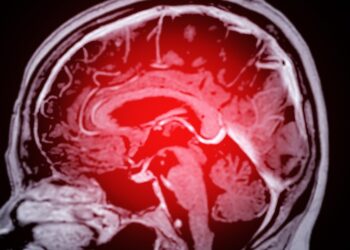

Paveldima hemoraginė teleangiektazija (HHT), dar vadinama Oslerio–Weberio–Rendu sindromu, yra reta genetinė liga, kuri pažeidžia kraujagysles. Šios ligos metu organizme formuojasi...